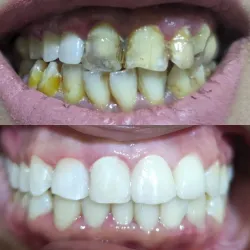

Full Mouth White Fillings

White Fillings